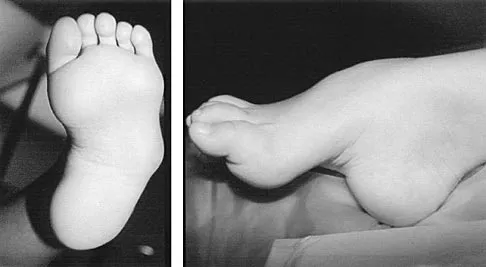

A 6-year-old girl has the bilateral foot deformity shown in Figure 1. There is no family history of disease. Examination reveals fixed hindfoot equinus, and muscle function testing shows strong posterior tibial function, fair plus anterior tibial function, poor peroneal function, and strong gastrocnemius function. A Coleman block test shows a correctable hindfoot. Nerve conduction velocity studies show diminished function in the peroneal and ulnar nerves on both sides. Pathologic changes found in a sural nerve biopsy include "onion bulb" formation, and DNA testing confirms the presence of a mutation in the MPZ gene, consistent with hereditary motor sensory neuropathy type III (HMSN-III). What is the best course of action?

Explanation

A newborn with bilateral talipes equinovarus undergoes serial manipulation and casting. What is the primary goal of manipulation?

Explanation